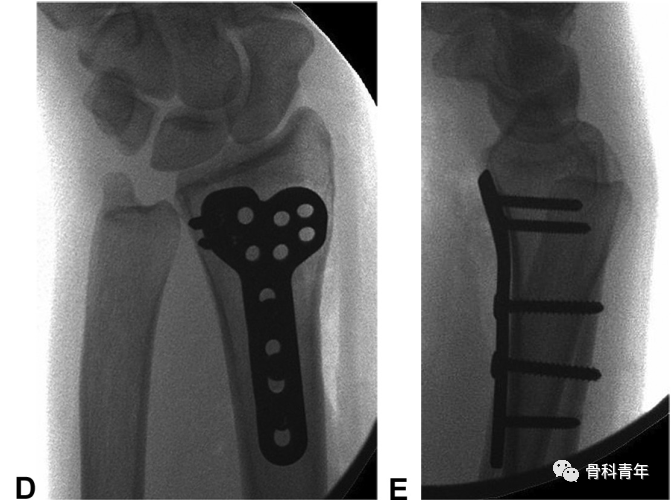

该病例采用2枚螺钉固定骨块后,钢板置入保护螺钉。

鉴于常规桡骨远端骨折钢板在固定该骨块上存在以下缺陷:一是采用桡侧腕屈肌入路,显露欠佳,二是掌侧锁定板螺钉大,对小骨块固定不确切,并可能将螺钉置入骨块间隙导致骨块移位。因此学者建议采用2.0mm或2.4mm锁定钢板特异性固定中柱骨块。此外,除支撑钢板外,采用2枚螺钉固定骨块后,中和钢板保护螺钉,也是一种内固定的可选方案。